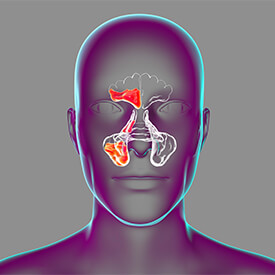

축농증(부비동염)은 부비동에 염증이 생겨 발생하는 질환입으로 급성과 만성으로 구분합니다.

급성 부비동염의 경우 약물 치료를 시행하고 충분한 치료가 어려운 만성 축농증은 수술을 고려합니다.

더불어 비중격만곡증, 비후성 비염 등의 동반된 코 질환이 있을 때도 수술 치료를 시행하여 근본적인 문제를 개선합니다.